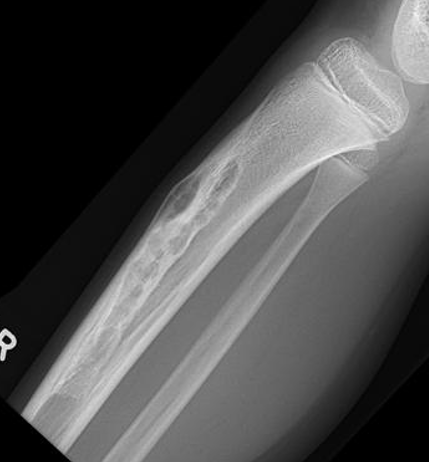

X-ray

Multiple small radiolucent lesions surrounded by sclerosis

Thickened cortex

Anterior cortex of tibial diaphysis +/- fibula